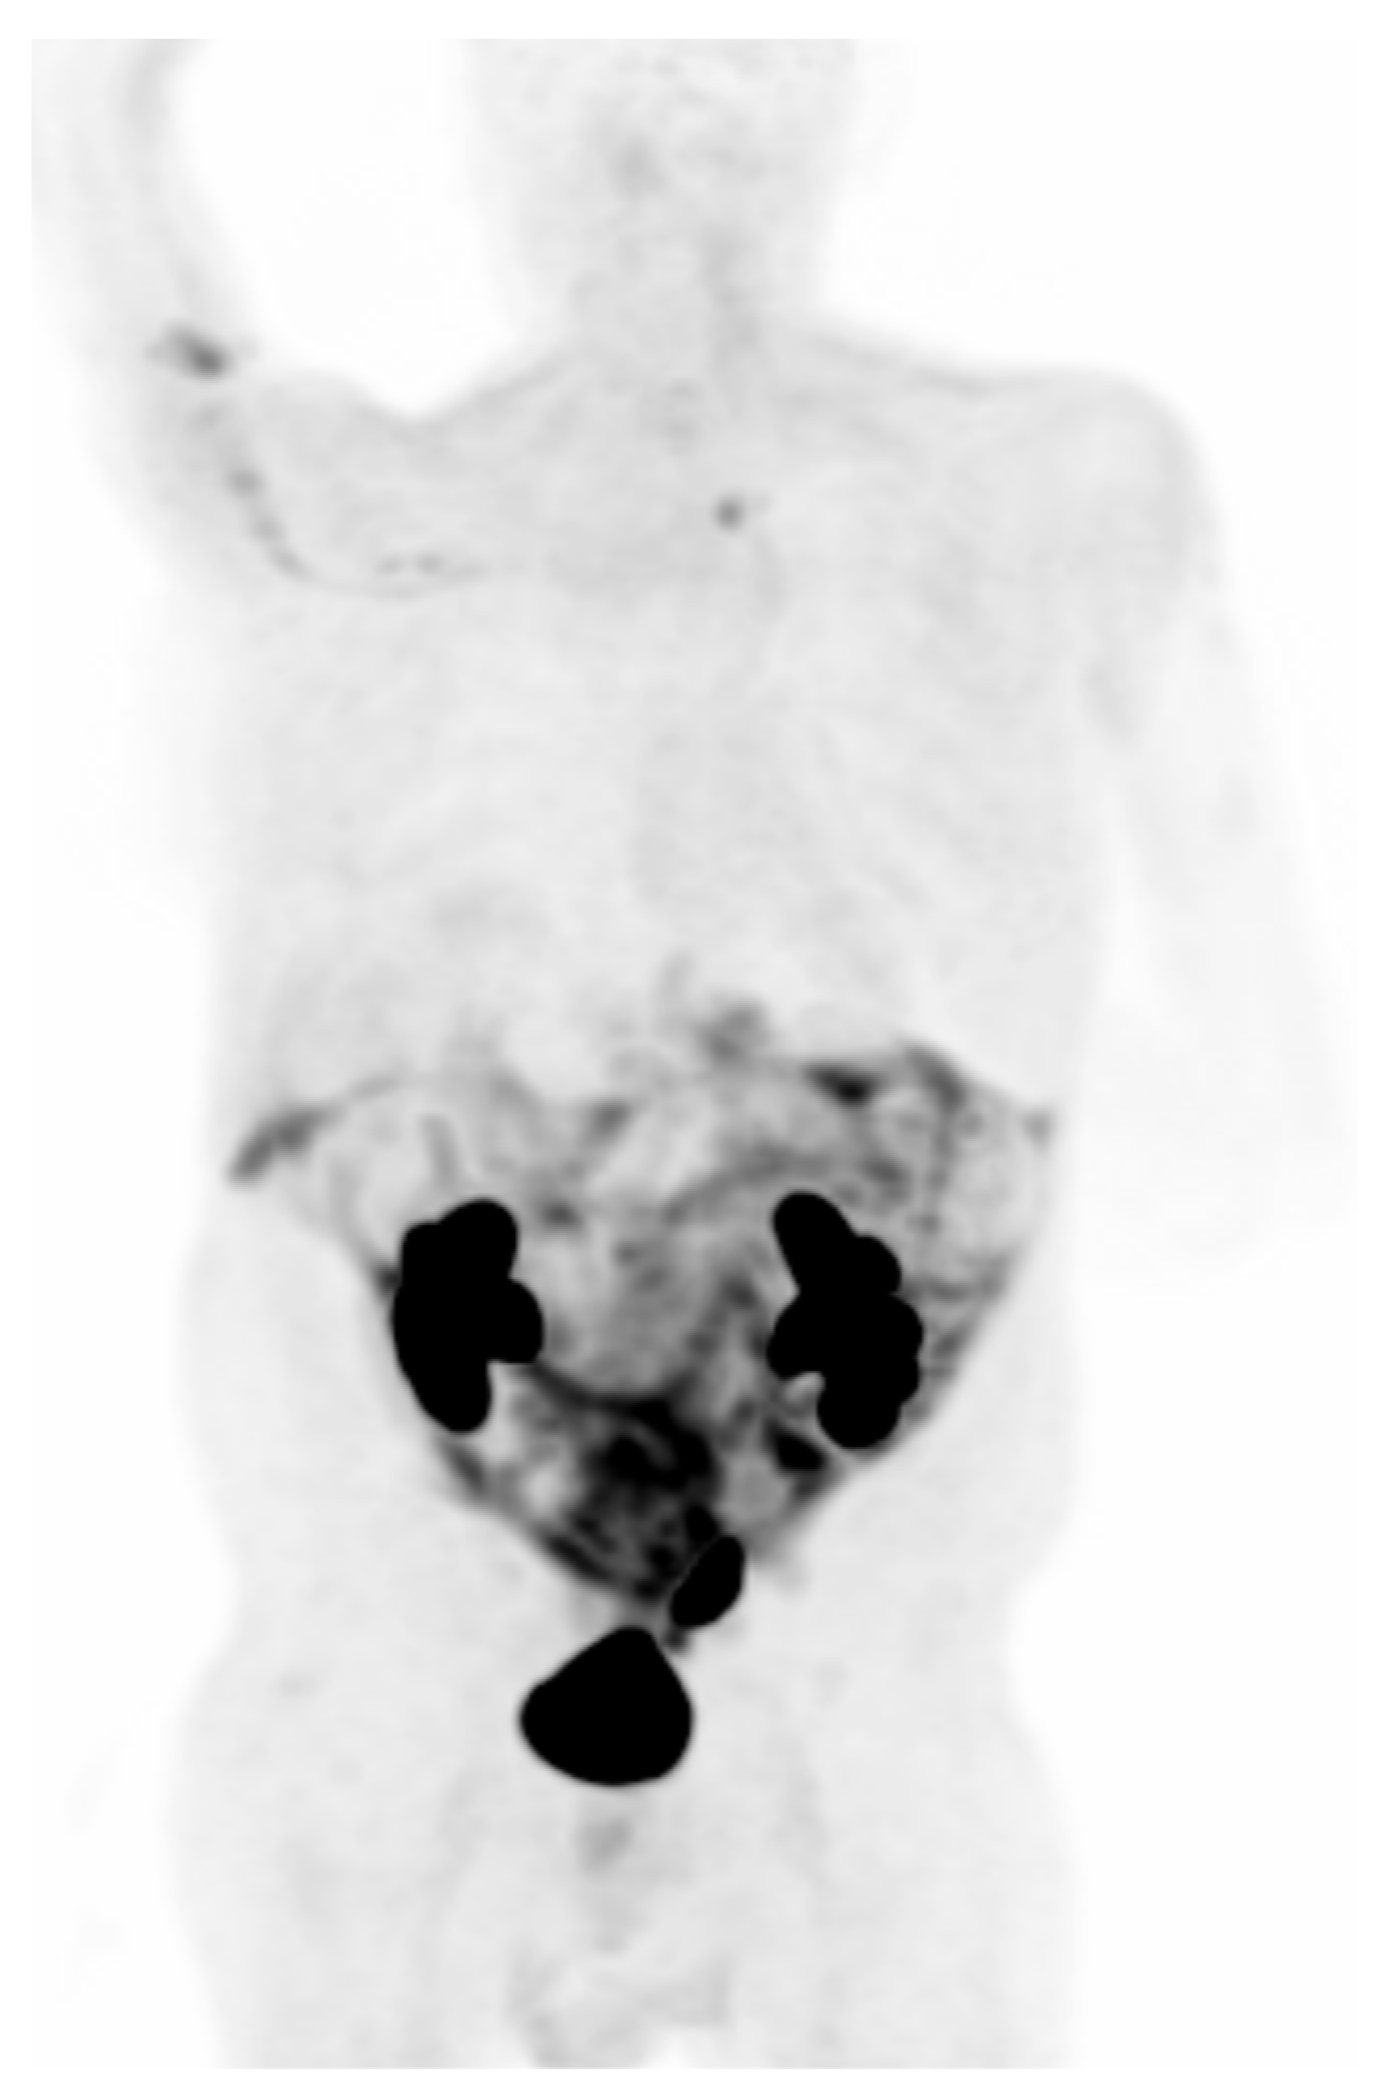

- Liu, J.; Dong, M.; Sun, X.; Li, W.; Xing, L.; Yu, J. Prognostic Value of 18F-FDG PET/CT in Surgical Non-Small Cell Lung Cancer: A Meta-Analysis. PLoS ONE 2016, 11, e0146195. [Google Scholar] [CrossRef]

- Paesmans, M.; Berghmans, T.; Dusart, M.; Garcia, C.; Hossein-Foucher, C.; Lafitte, J.J.; Mascaux, C.; Meert, A.P.; Roelandts, M.; Scherpereel, A.; et al. Primary tumor standardized uptake value measured on fluorodeoxyglucose positron emission tomography is of prognostic value for survival in non-small cell lung cancer: Update of a systematic review and meta-analysis by the European Lung Cancer Working Party for the International Association for the Study of Lung Cancer Staging Project. J. Thorac. Oncol. 2010, 5, 612–619. [Google Scholar] [CrossRef]

- Im, H.J.; Pak, K.; Cheon, G.J.; Kang, K.W.; Kim, S.J.; Kim, I.J.; Chung, J.K.; Kim, E.E.; Lee, D.S. Prognostic value of volumetric parameters of 18F-FDG PET in non-small-cell lung cancer: A meta-analysis. Eur. J. Nucl. Med. Mol. Imaging 2015, 42, 241–251. [Google Scholar] [CrossRef] [PubMed]

- Szyszko, T.A.; Yip, C.; Szlosarek, P.; Goh, V.; Cook, G.J. The role of new PET tracers for lung cancer. Lung Cancer 2016, 94, 7–14. [Google Scholar] [CrossRef] [PubMed]

- Wang, L.; Tang, G.; Hu, K.; Liu, X.; Zhou, W.; Li, H.; Huang, S.; Han, Y.; Chen, L.; Zhong, J.; et al. Comparison of 68Ga-FAPI and 18F-FDG PET/CT in the Evaluation of Advanced Lung Cancer. Radiology 2022, 303, 191–199. [Google Scholar] [CrossRef] [PubMed]

- Zhou, X.; Wang, S.; Xu, X.; Meng, X.; Zhang, H.; Zhang, A.; Song, Y.; Zhu, H.; Yang, Z.; Li, N. Higher accuracy of [68 Ga]Ga-DOTA-FAPI-04 PET/CT comparing with 2-[18F]FDG PET/CT in clinical staging of NSCLC. Eur. J. Nucl. Med. Mol. Imaging 2022, 49, 2983–2993. [Google Scholar] [CrossRef]